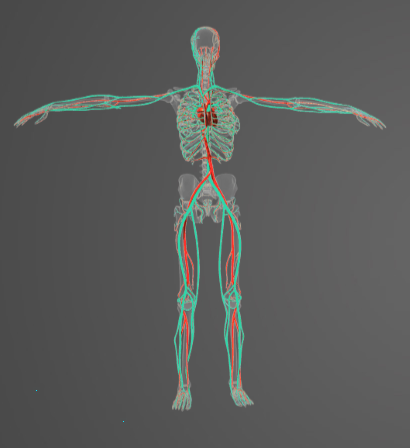

-

Question of

Určete:

-

sval podkožní

-

svaly šikmé

-

sval rombický velký a malý

-

široký sval zádový

-